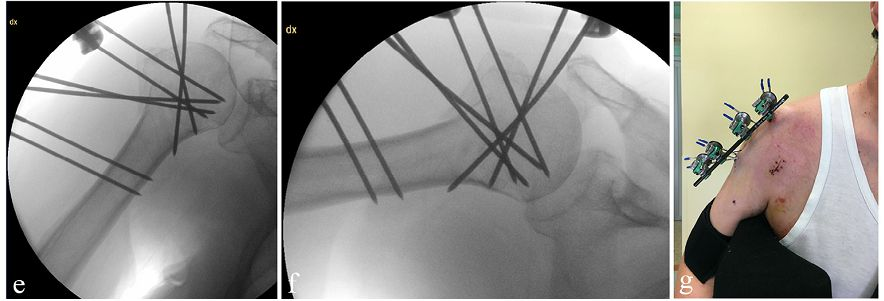

本文比较了2种固定方法

3组螺纹针固定 Vs 4组螺纹针固定

可见A和B相差就在于干骺端多了一组螺纹导针。理论上肯定是B组稳定性更好。

功能评分上B组(4组螺纹针)irCS评分打到92.82

如果把每组螺纹针看成是锁定螺钉的话,可以更好理解B结构的优势,相当于在干骺端植入一枚锁定螺钉,而外架相当于一块锁定板。